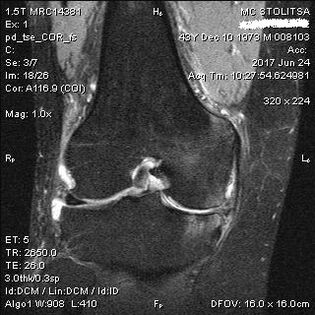

Diagnosis of osteoarthritis in the knee joint takes place in the office of a rheumatologist or orthopedist.The doctor examines the affected joint, palpates it, listens to complaints and asks additional questions.Performs several tests – for example, asking the patient to bend the leg or walk a few steps.Then, if it is necessary to clarify the stage of the disease or the nature of pathological changes, he will refer you to further examinations.For example, for computed tomography or radiography.